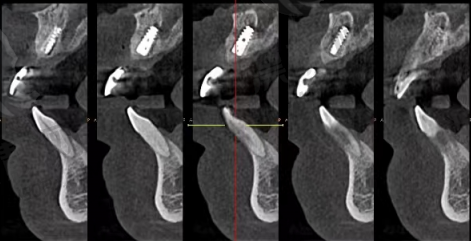

CBCT口腔三维影像扫描仪 | 高精度AI建模,3D立体成像 | 种植牙、正畸术前评估 |